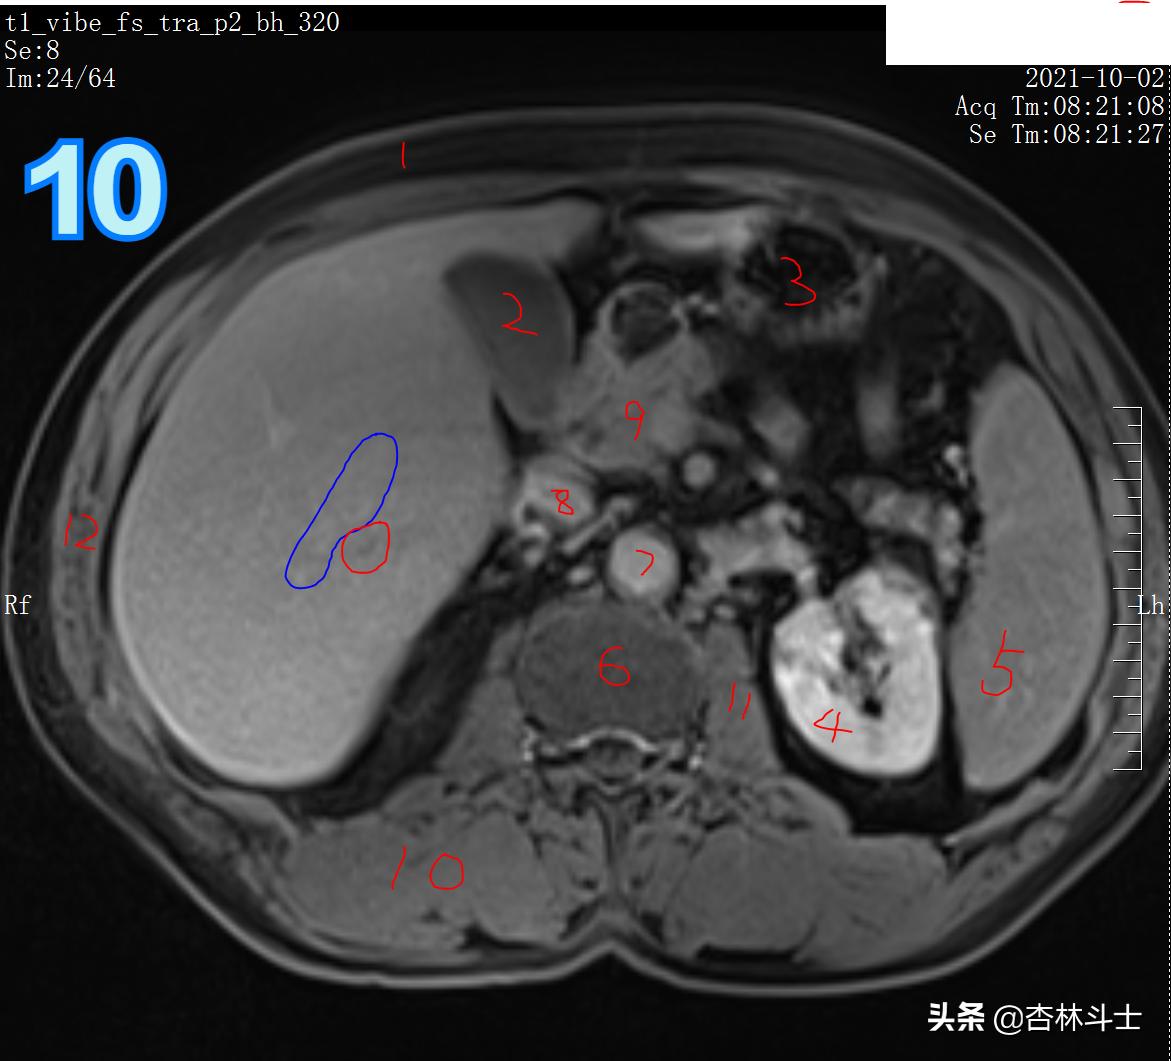

T1加权压脂平衡期

图10 红框病灶对比剂进一步廓清,呈略低信号。图中1、皮下脂肪 2、胆囊 3、胃腔 4、左肾 5、脾脏 6、脊柱 7、腹主动脉 8、下腔静脉 9、胰头 10、背部肌肉(竖脊肌)11、腰大肌 12、腹壁肌肉(腹外斜肌、腹内斜肌、腹横肌)